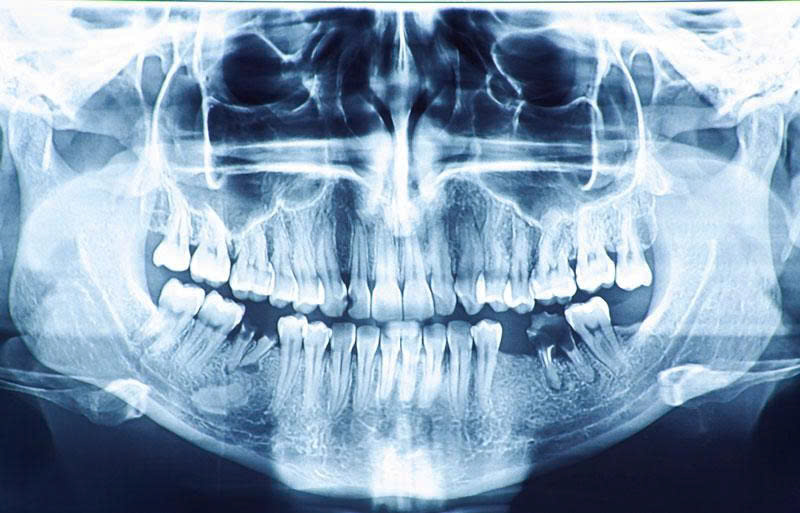

Khi có các dấu hiệu trên, hãy đến Nha Khoa SV để được chụp phim, kiểm tra và chẩn đoán chính xác.

Khám và chụp phim X-quang:

-

Bác sĩ kiểm tra tổng quát, chụp phim để xác định tình trạng tủy và số lượng ống tủy. -

✨ Tư vấn, khám và chụp phim X-quang hoàn toàn miễn phí.